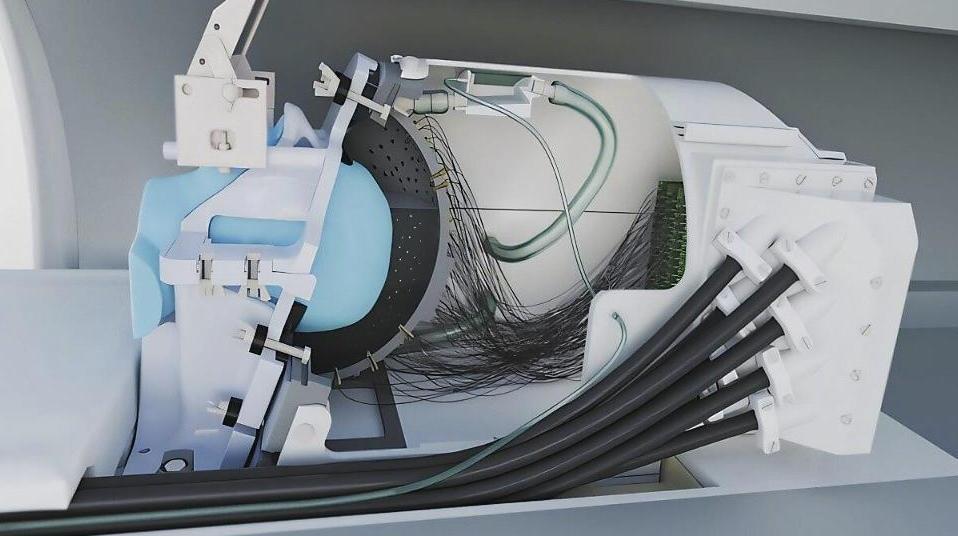

超聲波頭盔可進(jìn)行無創(chuàng)深部腦刺激

2025-09-10 07:35:20